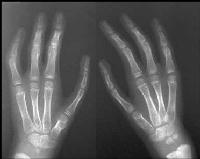

| Case 3. (case of unknown surgeon). The index fingers were probably narrow to begin with, and the current metacarpal length detract from the final result. |